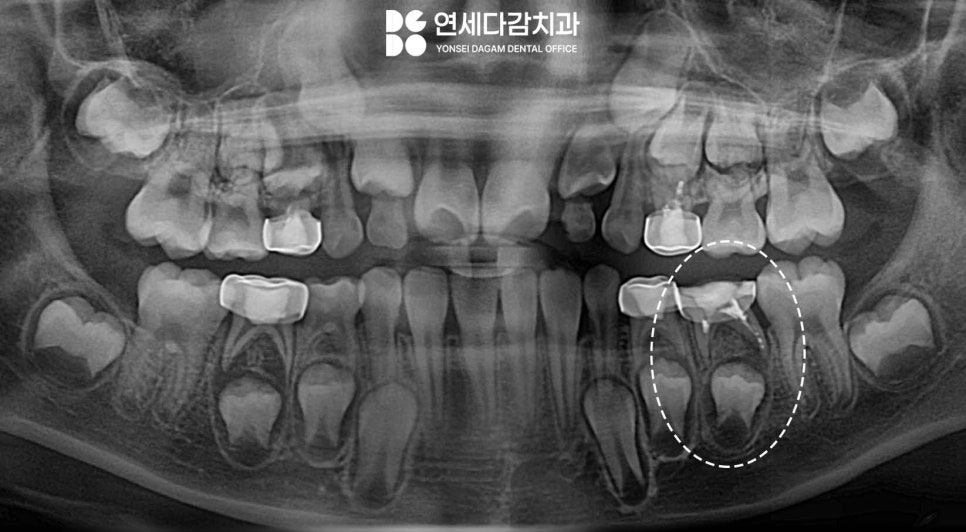

마취 후 가능한 손상이 없도록 크라운을

제거한 뒤 새로 제작합니다.

이 과정에서는 세심한 주의가 필요합니다.

무리한 힘을 가하지 않고 단계적으로

접근해야 됩니다.

기존 크라운을 조심스럽게 제거하고

치아 상태를 정확히 평가한 후

새로운 크라운을 맞춤 제작합니다.

그 결과 통증과 고름이

해소될 수 있게 됩니다.